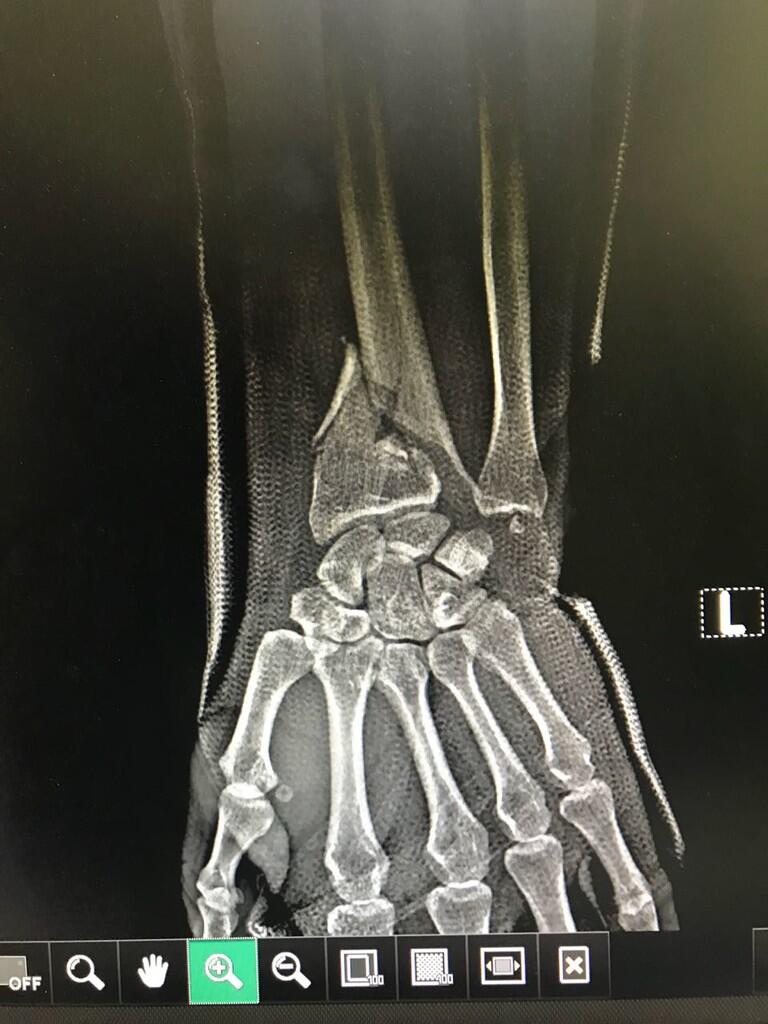

Pada saat H-1 lebaran kemarin kakak saya kecelakaan motor jadi terjatuh dan patah tangannya, dan setelah di rongent ternyata penjelasannya ada 2 patah tulang dan 1 bagian yg retak.

Setelah 1minggu kakak saya merasa tidak ada perubahan dan melakukan rongent kembali dan ternyata posisi tulang menjauh bukan merapat.

sehingga disarankan utk operasi karena sudah terlalu lama prosesnya,